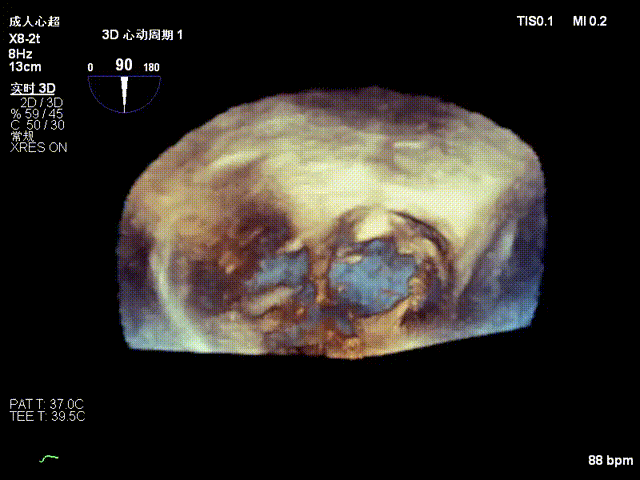

Echocardiographic findings indicated: Type IIIB quadrileaflet tricuspid malformation with extremely severe tricuspid regurgitation (5+, vena contracta: 16.1 mm on average). Regurgitant orifices were located at the anterior-septal, central, and posterior-septal regions, with a 11 mm central gap, leaflet tethering (tethering height: 10 mm), and tricuspid annular dilatation (mean annular diameter: 53 mm). The inferior vena cava diameter was approximately 25 mm, and RV FAC was 40%.

Baseline regurgitation after anesthesia